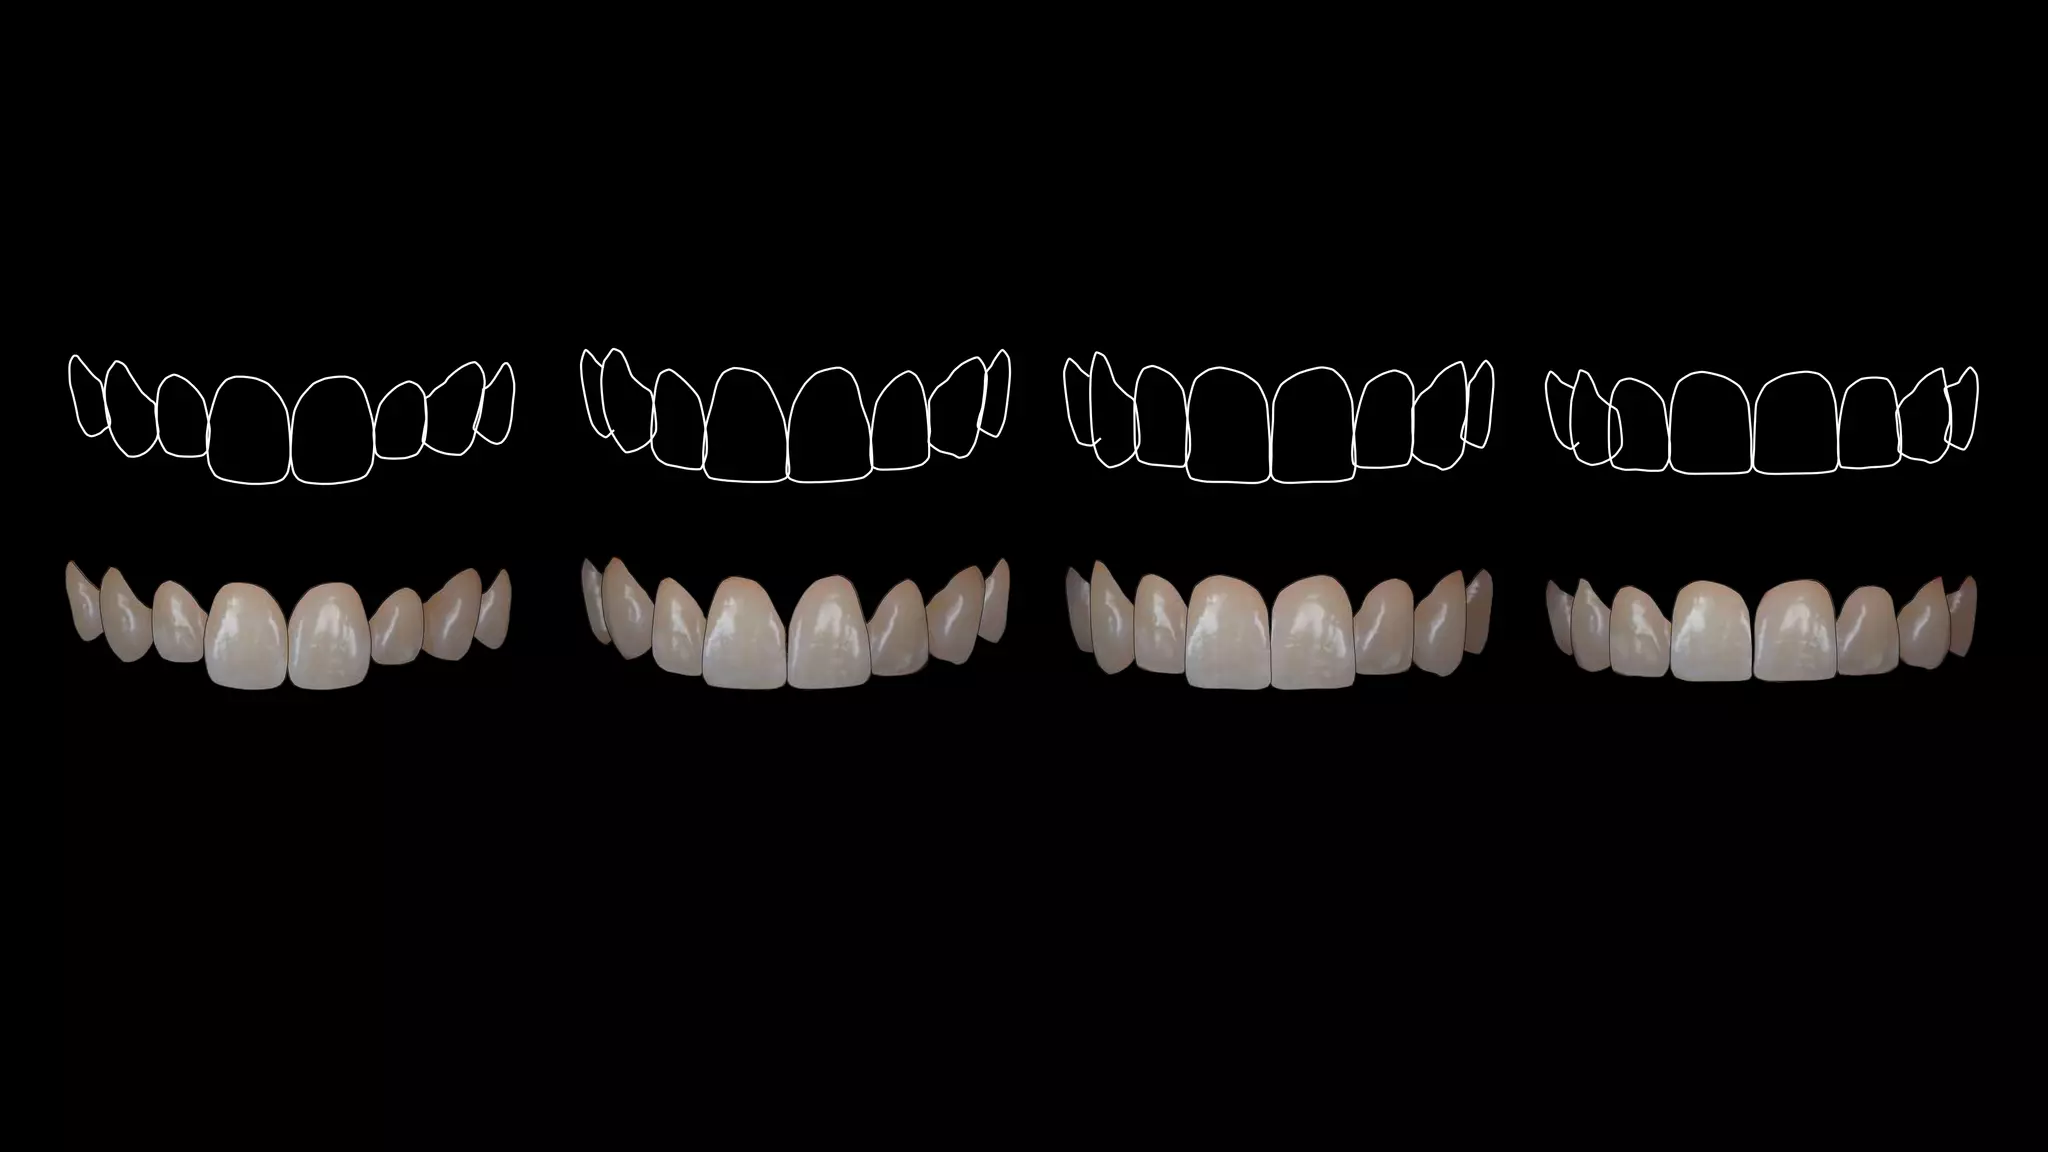

Discussion on tooth proportion guides and aesthetic goals, including percentages for ideal ratios.

Exploration of various shapes and their associated psychological traits including strong, calm, and artistic attributes.